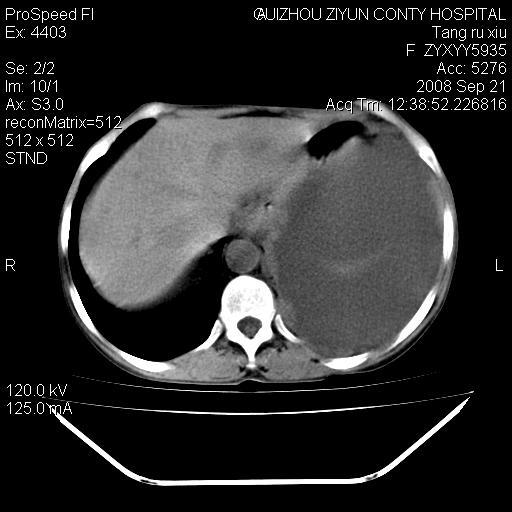

f、57岁,上腹痛.2月,近来胸闷。2月前在外院摄胸片示左侧胸腔少量积液。

(患者腹痛入院,欲吐,临床医生说禁饮,所以没有口服对比剂)

考虑----左侧胸腹腔积液----压迫性肺不张----心包积液---肝脏多发低密度影-----穿刺抽液后复查

左侧胸壁见一结节影,肝脏多发低密度影,左侧胸腔大量积液。建议增强

1)考虑左侧肺癌侵犯纵隔,左侧胸膜、肝脏及腹膜后淋巴结转移。2)左侧胸腔积液。3)心包积液。

肝脏大小形态尚可,其实质内可见多发大小不等的低密度影,边缘模糊。肝门区结构紊乱,腔静脉腹主动脉旁可见多发软组织密度影,部分融合成团块状,并向下延伸。胰腺及十二指肠结构显示不清。腹腔内脐后肠管走形僵硬,管壁可见增厚。盆腔内可见多个淋巴结影。所扫层面左侧胸腔可见大量弧形水样密度影,其内侧可见被压缩的肺组织影。左侧胸壁可见一小结节样软组织密度影,边缘模糊。心脏纵隔向右侧移位。心脏包膜内可见囊样低密度影,其内侧心房室周围可见一圈气体样密度影。纵隔内大血管旁可见多发软组织团块影,部分融合。

1.腹膜后淋巴瘤侵及肝脏,肺内及纵隔内多发转移。2.左侧大量胸腔积液并压缩性肺不张。3.心包脓肿可能,转移不除外。4.脐后局部肠管管壁增厚,考虑炎症可能,肿瘤不除外。

左侧中心型肺癌并胸膜及心包转移。肝内转移,腹膜后淋巴结转移。